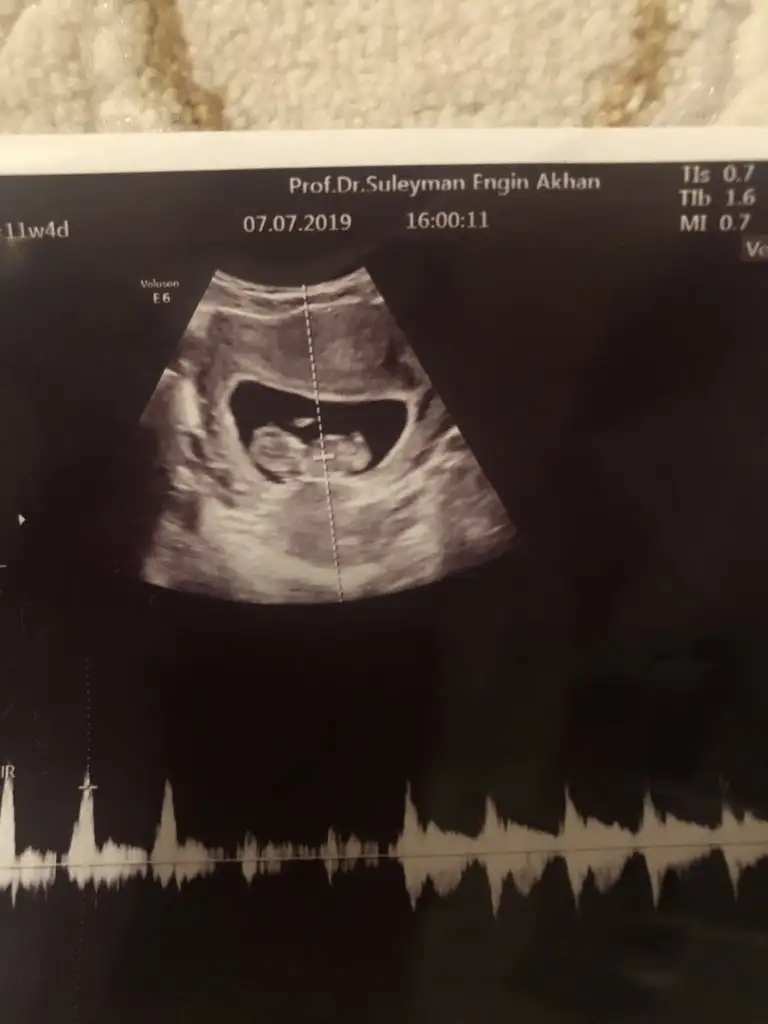

Nub yöntemine göre cinsiyet tahmini

15 haftadasınız dr yorum yapmadımı 11 yada 12 hafta olmalı nub için

Saglıkla gelsin bebeginiz inşallah daha önce sanki size tahminde bulunmuştum 11-12 haftalık usg nize erkek tahmini etmiştim nub teorisinde dimi